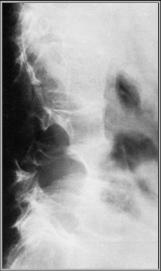

Neurofibromatosis